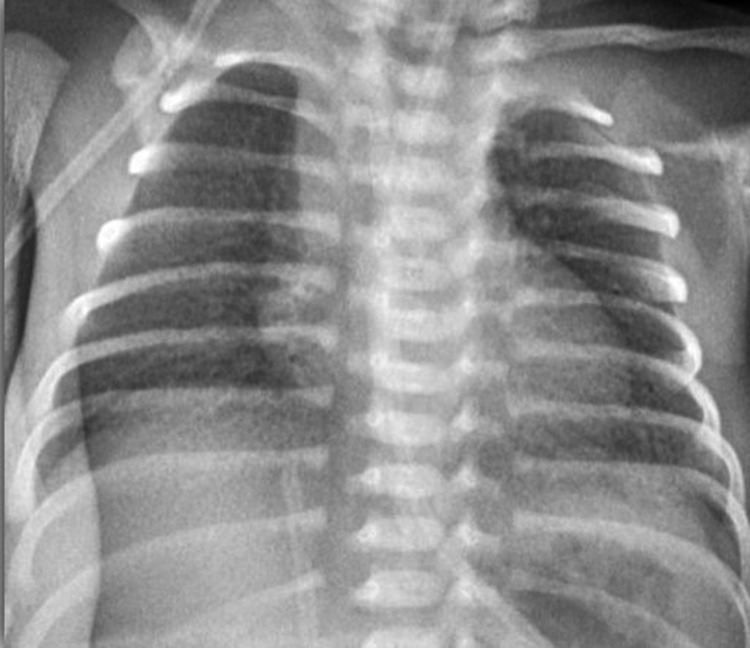

Picture 5.

Grade 1—X ray

Picture 6.

Grade 2—X ray

Picture 7.

Grade 3—X ray

Picture 8.

Grade 4—X ray

Radiographic findings were classified into four stages, from mild to severe disease [10] Table 2 and Pictures 5, 6, 7, 8.

On plain X-ray radiography, there is reticulogranular or ground-glass opacification, progressive hypoaeration, and air bronchograms [11].